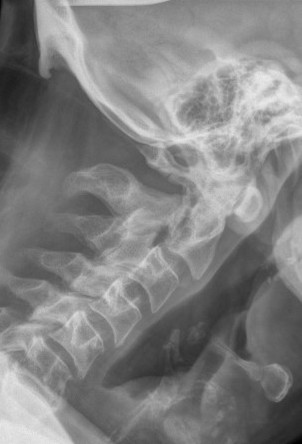

Xray

Hangman's fracture reduced and held in halo-vest

Post halo flexion and extension views demonstrating fracture stability